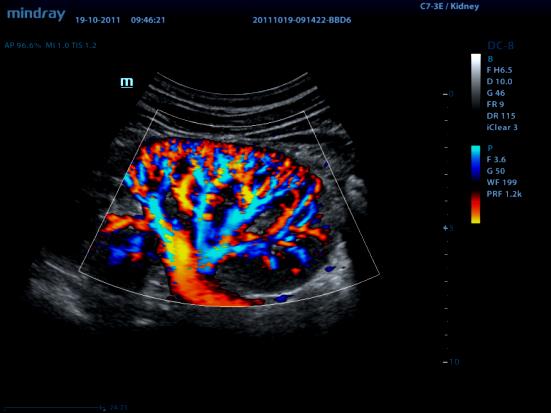

CFM (CDI, CDV, CD, CF, ЦДК и т.д.) – режим цветового допплеровского картирования по скорости

В режиме цветового допплеровского картирования по скорости (ЦДК) изображение строится также как и в B-режиме. Отличительной особенностью режима ЦДК является цветовое отображение информации о скорости и направлении движения структур в выделенной пользователем области (окно опроса). Режим ЦДК обладает ярко выраженной зависимостью от величины допплеровского угла.

d8ed0e61a63ea3510f2186998867c073d4e18264.jpg